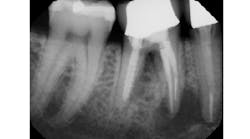

Aggressively debriding granulation/cystic tissue after tooth extraction is important for the removal of bacteria, inducing angiogenesis, and the promotion of the blood clot. This is especially true when subsequent grating and dental implants are in the treatment plan. The importance of thorough socket debridement should be second to inducing a transient or permanent injury via instrument penetration into the nerve space. According to Oral Surgeon Gregg Jacob, DMD, even if large lesions are present (figure 1), “Leaving granulation tissue and allowing the body to resorb pathology is more prudent than risking nerve injury.”

Figure 1: Large periapical area near the IAN prior to tooth extraction

In many cases, removing these lesions in their entirety will increase the risk of canal penetration (figure 2) and subsequent paresthesia (figure 3).